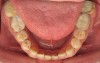

Figure 3 through Figure 7 Preoperative retracted, occlusal, and lingual views. Note the extreme acid erosion, with lost occlusal and lingual enamel.

Figure 3

Figure 4

Figure 5

Figure 6

Figure 7

When viewing his maxillary teeth from an occlusal and lingual view, one can see the erosion and wear (Figure 4, Figure 6, and Figure 7), and it becomes evident just how collapsed he actually is. This patient shows more teeth on his left side and less on the right when smiling, and the shortness and color of his teeth contributes to a definite aging of his smile. Additionally, his lips appear less full without the lip support of the lost tooth structure. The patient had Class I molar relationships on both the right and left sides, and a posterior open bite on his right side in the area of teeth Nos. 4 through 6 (Figure 8 and Figure 9). There was no crowding evident and both arches were found to have lingually inclined teeth, which may have contributed to his wear. It was also noted that his posterior teeth were worn down with a very flat anatomy and lacked proper functional guidance.